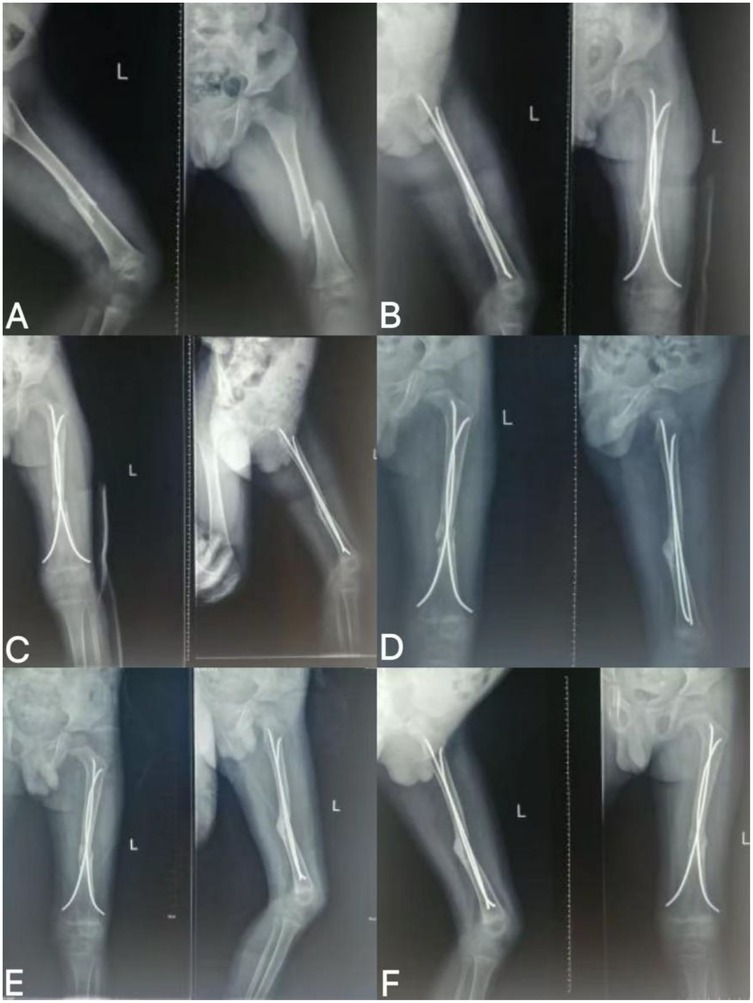

Figure 1. Imaging findings at follow-up after FIN surgery for left femoral shaft fracture. (A) Preoperative fracture; (B) 1 month after fracture surgery; (C) 2 months after fracture surgery; (D) 3 months after fracture surgery; (E) 5 months after fracture surgery; (F) 7 months after fracture surgery.

The patient, a 4-year-old male, sustained a left femoral shaft fracture (AO/OTA classification 32A2) secondary to trauma from a motor vehicle accident and underwent emergent intramedullary nailing (FIN) fixation. Subsequent serial radiographic evaluations during regular postoperative follow-up demonstrated impaired callus formation, progressive widening of the fracture gap, and disruption of cortical continuity, fulfilling the U.S. Food and Drug Administration (FDA) criteria for nonunion diagnosis—defined as persistent absence of radiographic healing signs for at least 9 months post-injury without progression over three consecutive months (Table 1) (17). Consequently, the parents declined the orthopedic recommendation for revision surgery due to concerns regarding anesthesia-associated risks, surgical morbidity, and economic burdens (18). This preference for nonoperative management was informed by age-related physiological immaturity, which may heighten anesthesia vulnerability and elevate risks of growth disturbances following reoperation (19). Conservative approaches typically entail prolonged immobilization (estimated duration 6–12 months or longer), exhibiting variable efficacy with potential complications including joint stiffness and muscular atrophy (17).